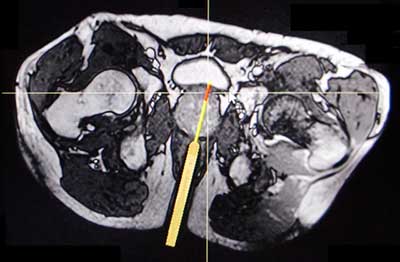

Figure 3

Axial T2-WI of in-bore MRI guided transrectal prostate biopsy in the same patient and at the same level as Figures 1 and 2. The patient initially underwent a systematic transrectal ultrasound guided prostate biopsy but the pathology result showed no malignancy. Because of the persistently rising PSA and the difficult location of the suspicious lesion, an in-bore MRI guided transrectal prostate biopsy was performed. The position of the transrectal needle guide (thick line) and the tru-cut biopsy needle (fine line) are demonstrated on the T2-WI and confirm that the suspicious lesion is sampled correctly. Two biopsy cores were taken, and the pathology result revealed Gleason 4 + 4 prostate cancer in both of them.